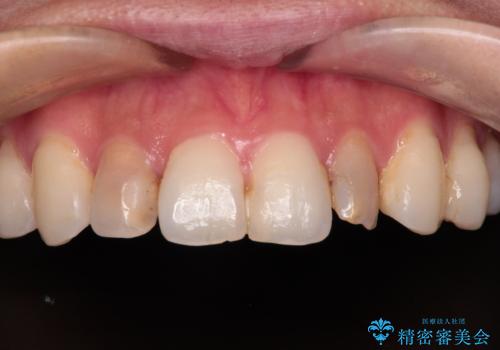

- 前歯の変色が気になるので、きれいにしたいことを主訴として来院された患者様です。

もともと矮小歯であることが気になっており、他院で矯正治療を行い、スペースを作っている状態でした。

根管治療をしているため、歯の変色が認められます。

もともと矮小歯で歯の大きさが小さいことが気になっていましたが、改善されて満足されました。